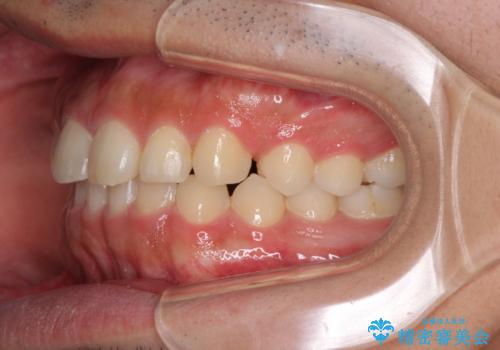

インビザラインによる、すきっ歯の改善

- 前歯がすきっ歯であることを気にして来院された患者様です。

下の前歯がほとんど隠れてしまうくらいの深い咬み合わせであったので、インビザラインを用いて、咬み合わせの高さを改善しながら隙間を閉じていくこととしました。

咬合力で上の前歯が前方に押し出されるようにして隙間ができていましたが、矯正治療により全て閉じることができました。

深い咬み合わせも多少改善され、隙間も閉じたことで、前方に出ていた前歯が引っ込んだため、口も閉じやすくなったとのことでした。